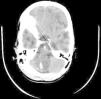

Tomografía axial computarizada craneal: en la región inferior del IV ventrículo se visualiza una masa hipodensa, de 25mm de diámetro, con 2 nódulos situados en el margen posterolateral derecho de la lesión descrita, que captan contraste de forma intensa y a los que les llegan unas estructuras vasculares.